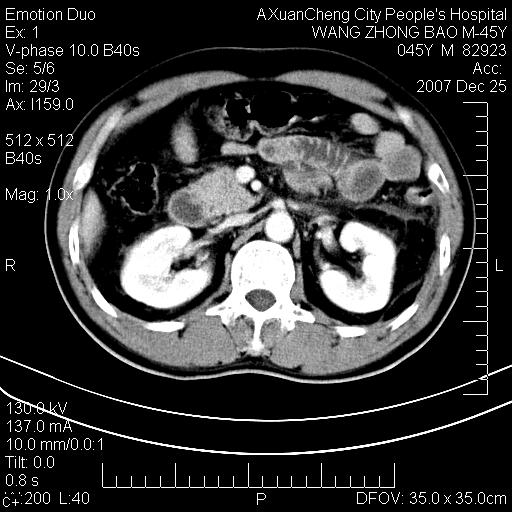

以下是引用卜一在2007-12-25 14:07:00的发言:[br]胰头钩部略增大,与十二指肠壶腹部关系密切,其内明显见软组织密度肿块,明显强化,但肠壁较光滑 柔软。考虑:炎性增生!建议消炎后复查!待除外壶腹部腺癌!

以下是引用zjzjr在2007-12-25 13:35:00的发言:[br]考虑正常的十二指肠乳头部,建议胃镜检查.

以下是引用qiuleiyu在2007-12-25 18:14:00的发言:[br]胰腺增大,周边渗出改变,肾前筋膜明显增厚,示少量积液.胆囊壁毛糙,周边少许渗出,胆总管壁厚,异常强化,然扩张不明显.结合病程急短;考虑;胆管炎,胆囊炎,胆源性胰腺炎可能大,请结合实验室检查及随访.

以下是引用lisihao在2007-12-25 14:23:00的发言:[br]急性水肿型胰腺炎[br]依据:1、胰腺弥漫性肿大,边缘稍毛糙;[br] 2、双侧肾周筋膜增厚,尤以左侧为甚(重要征象)[br] 3、双侧后胸膜增厚(刺激性炎症);[br] 4、结合病史,查血尿淀粉酶应该可以确诊。